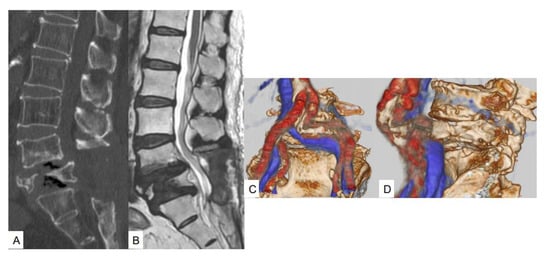

2.3. Preoperative Imaging

2.4. First Surgery and Postoperative Images